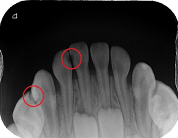

咬合面 X 光片(Occlusal X-rays)

拍攝範圍涵蓋整個上顎或下顎牙齒的咬合面。